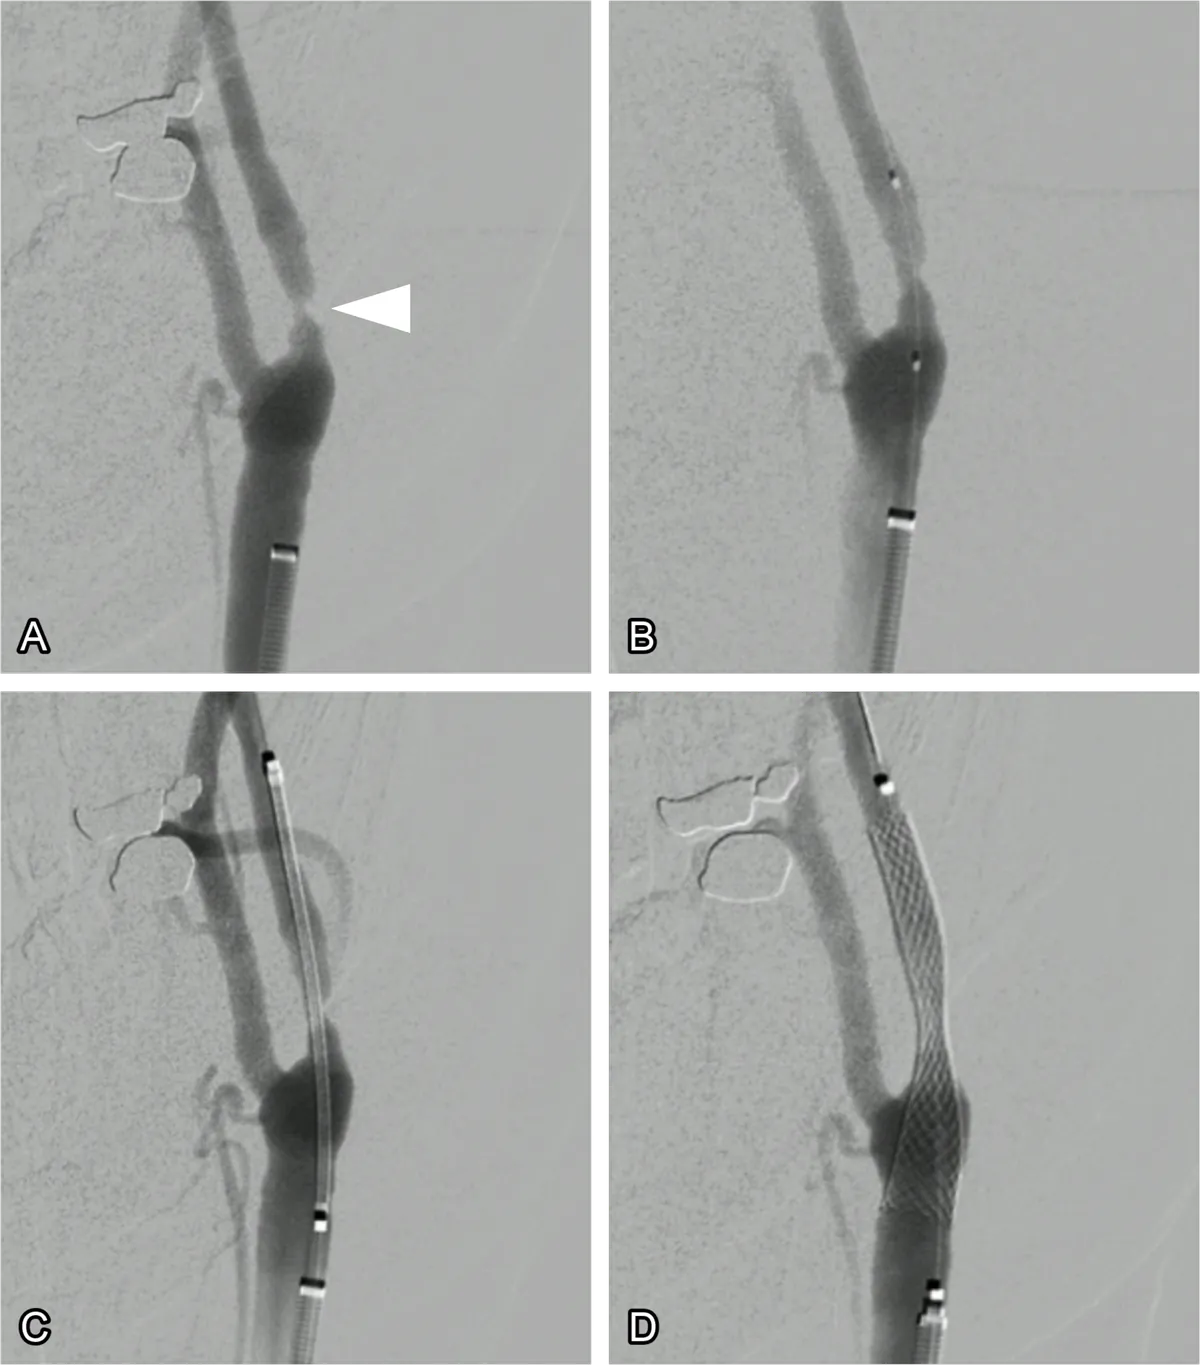

A small balloon may be used to widen the artery before placing the stent. The stent is then positioned across the narrowed segment (fig. 1). Once expanded, it stays in place permanently, acting as a scaffold that keeps the artery open. Modern procedures also use protection devices or flow-reversal systems to reduce the chance of plaque debris travelling into the brain during the procedure.

Figure 1: Carotid stenting. (A) Angiography of the carotid artery showing a narrowing (arrowhead). (B) A balloon has been inserted into the narrowing to expand it. (B) The stent is then inserted but is constrained within its container sheath. (C) The stent is unsheathed across the stenosis.